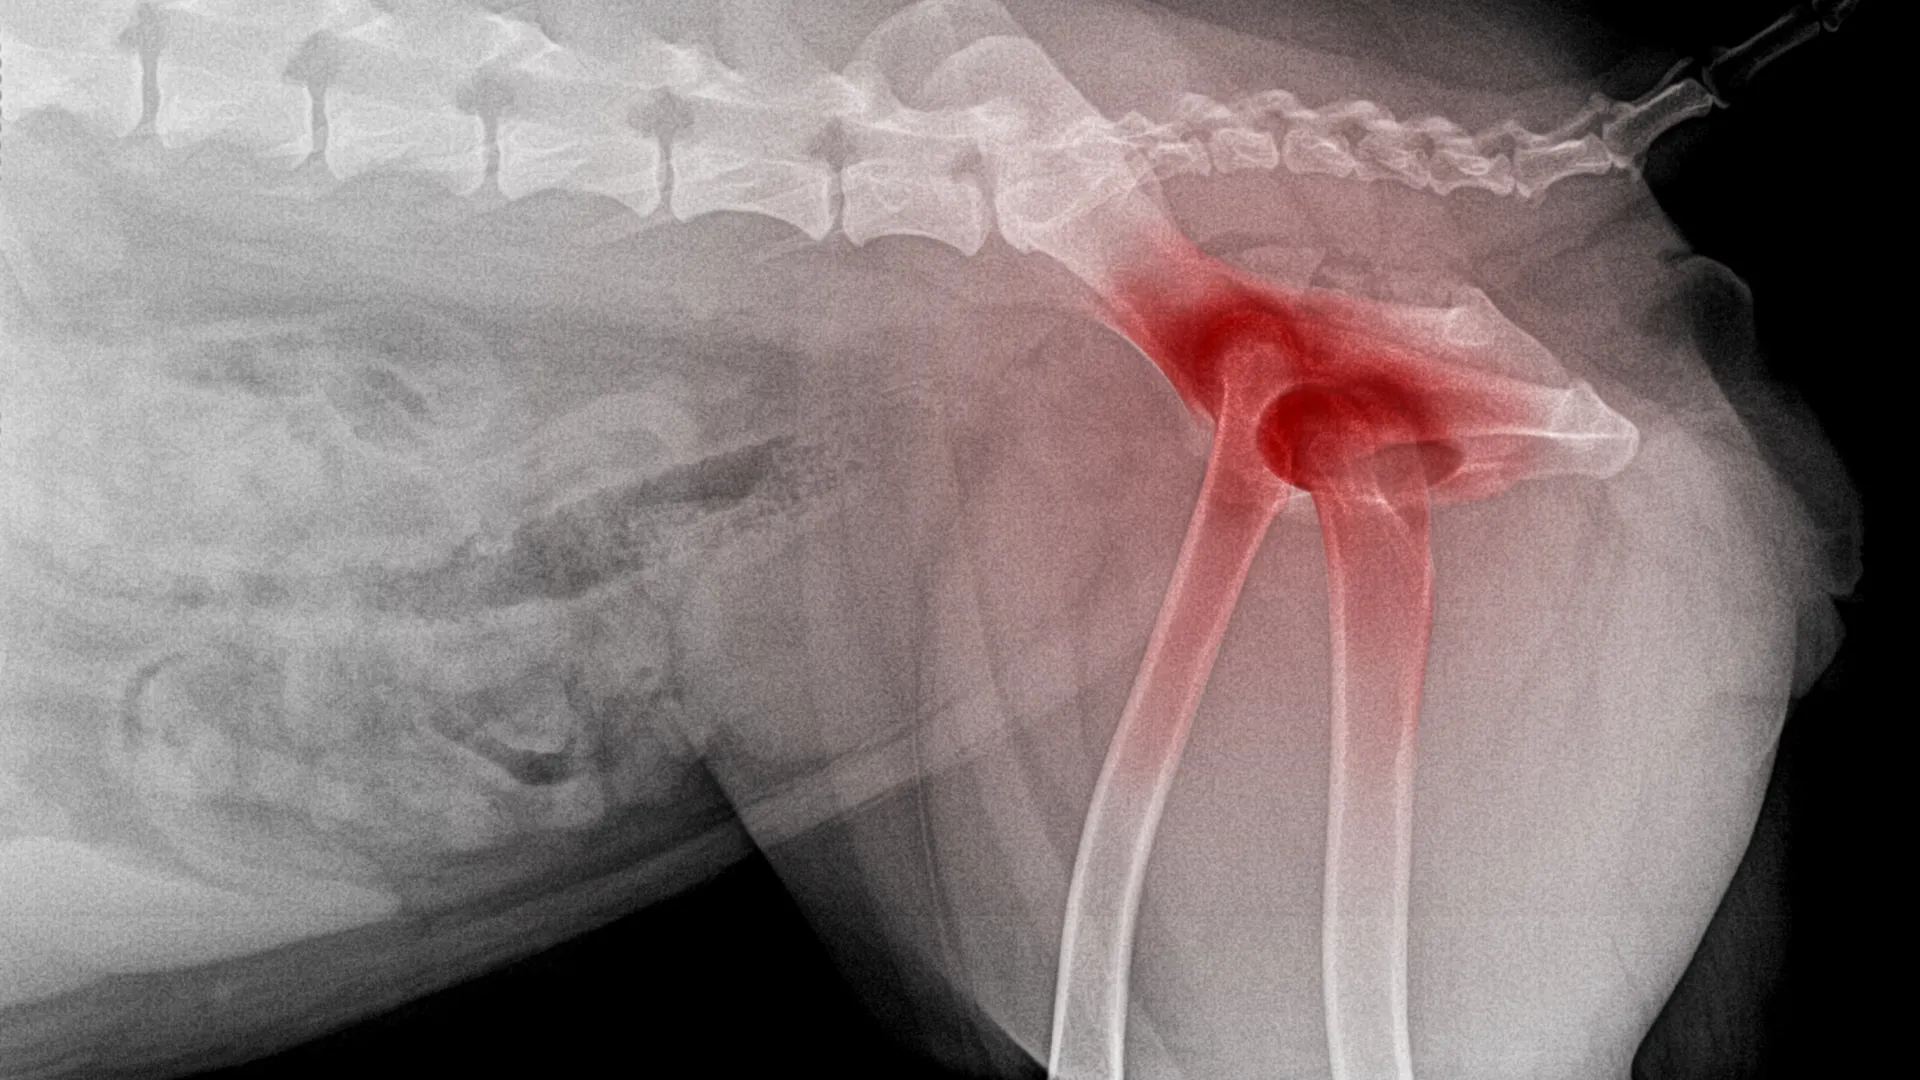

X-Rays (Radiographs)

X-rays are the main way to confirm hip dysplasia. Your dog will need to be sedated so the vet can position the legs correctly. They use extended-leg views to see how well the hip joint fits together.